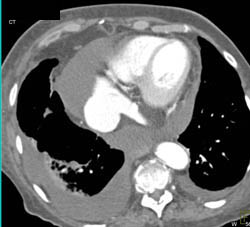

Diseased Leaflet Aortic Valve